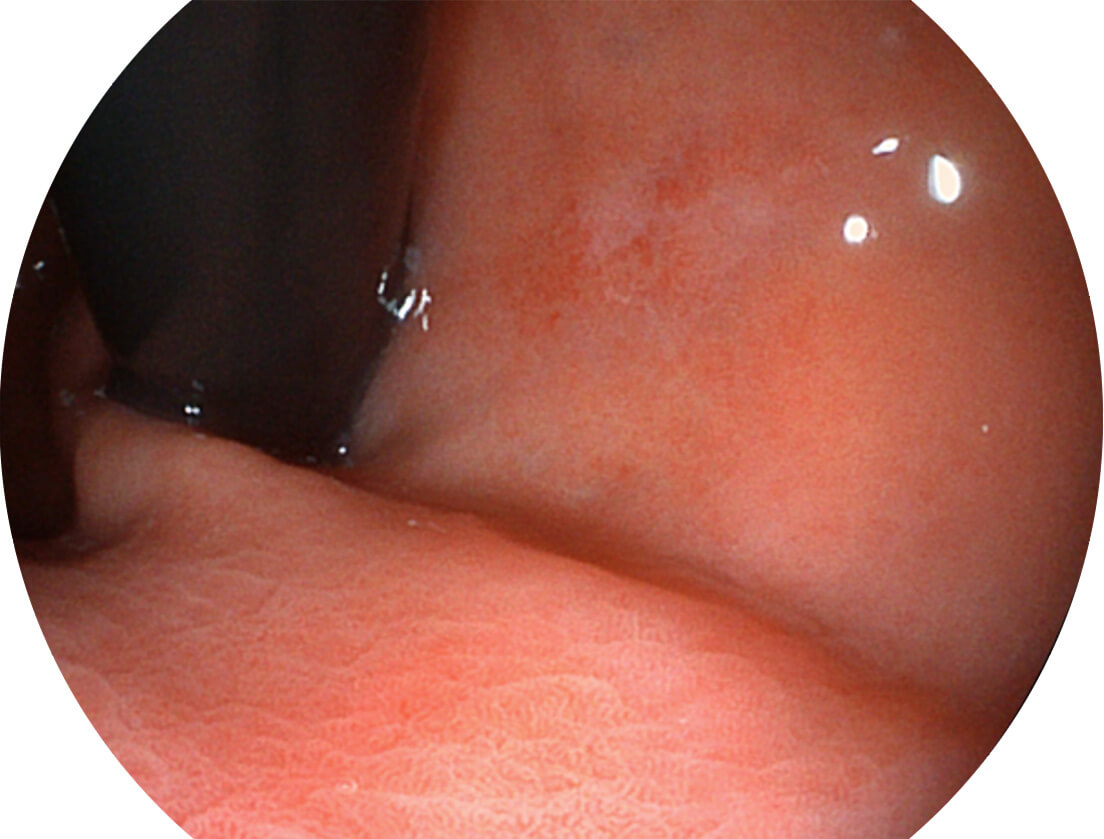

图像具有高亮度、高黏膜血管颜色对比度的特点,且不改变粘液、食物残渣、粪便的基本颜色,可在中远景下进行观察,助力消化道早期疾病的诊断。

SFI图像

白光图像